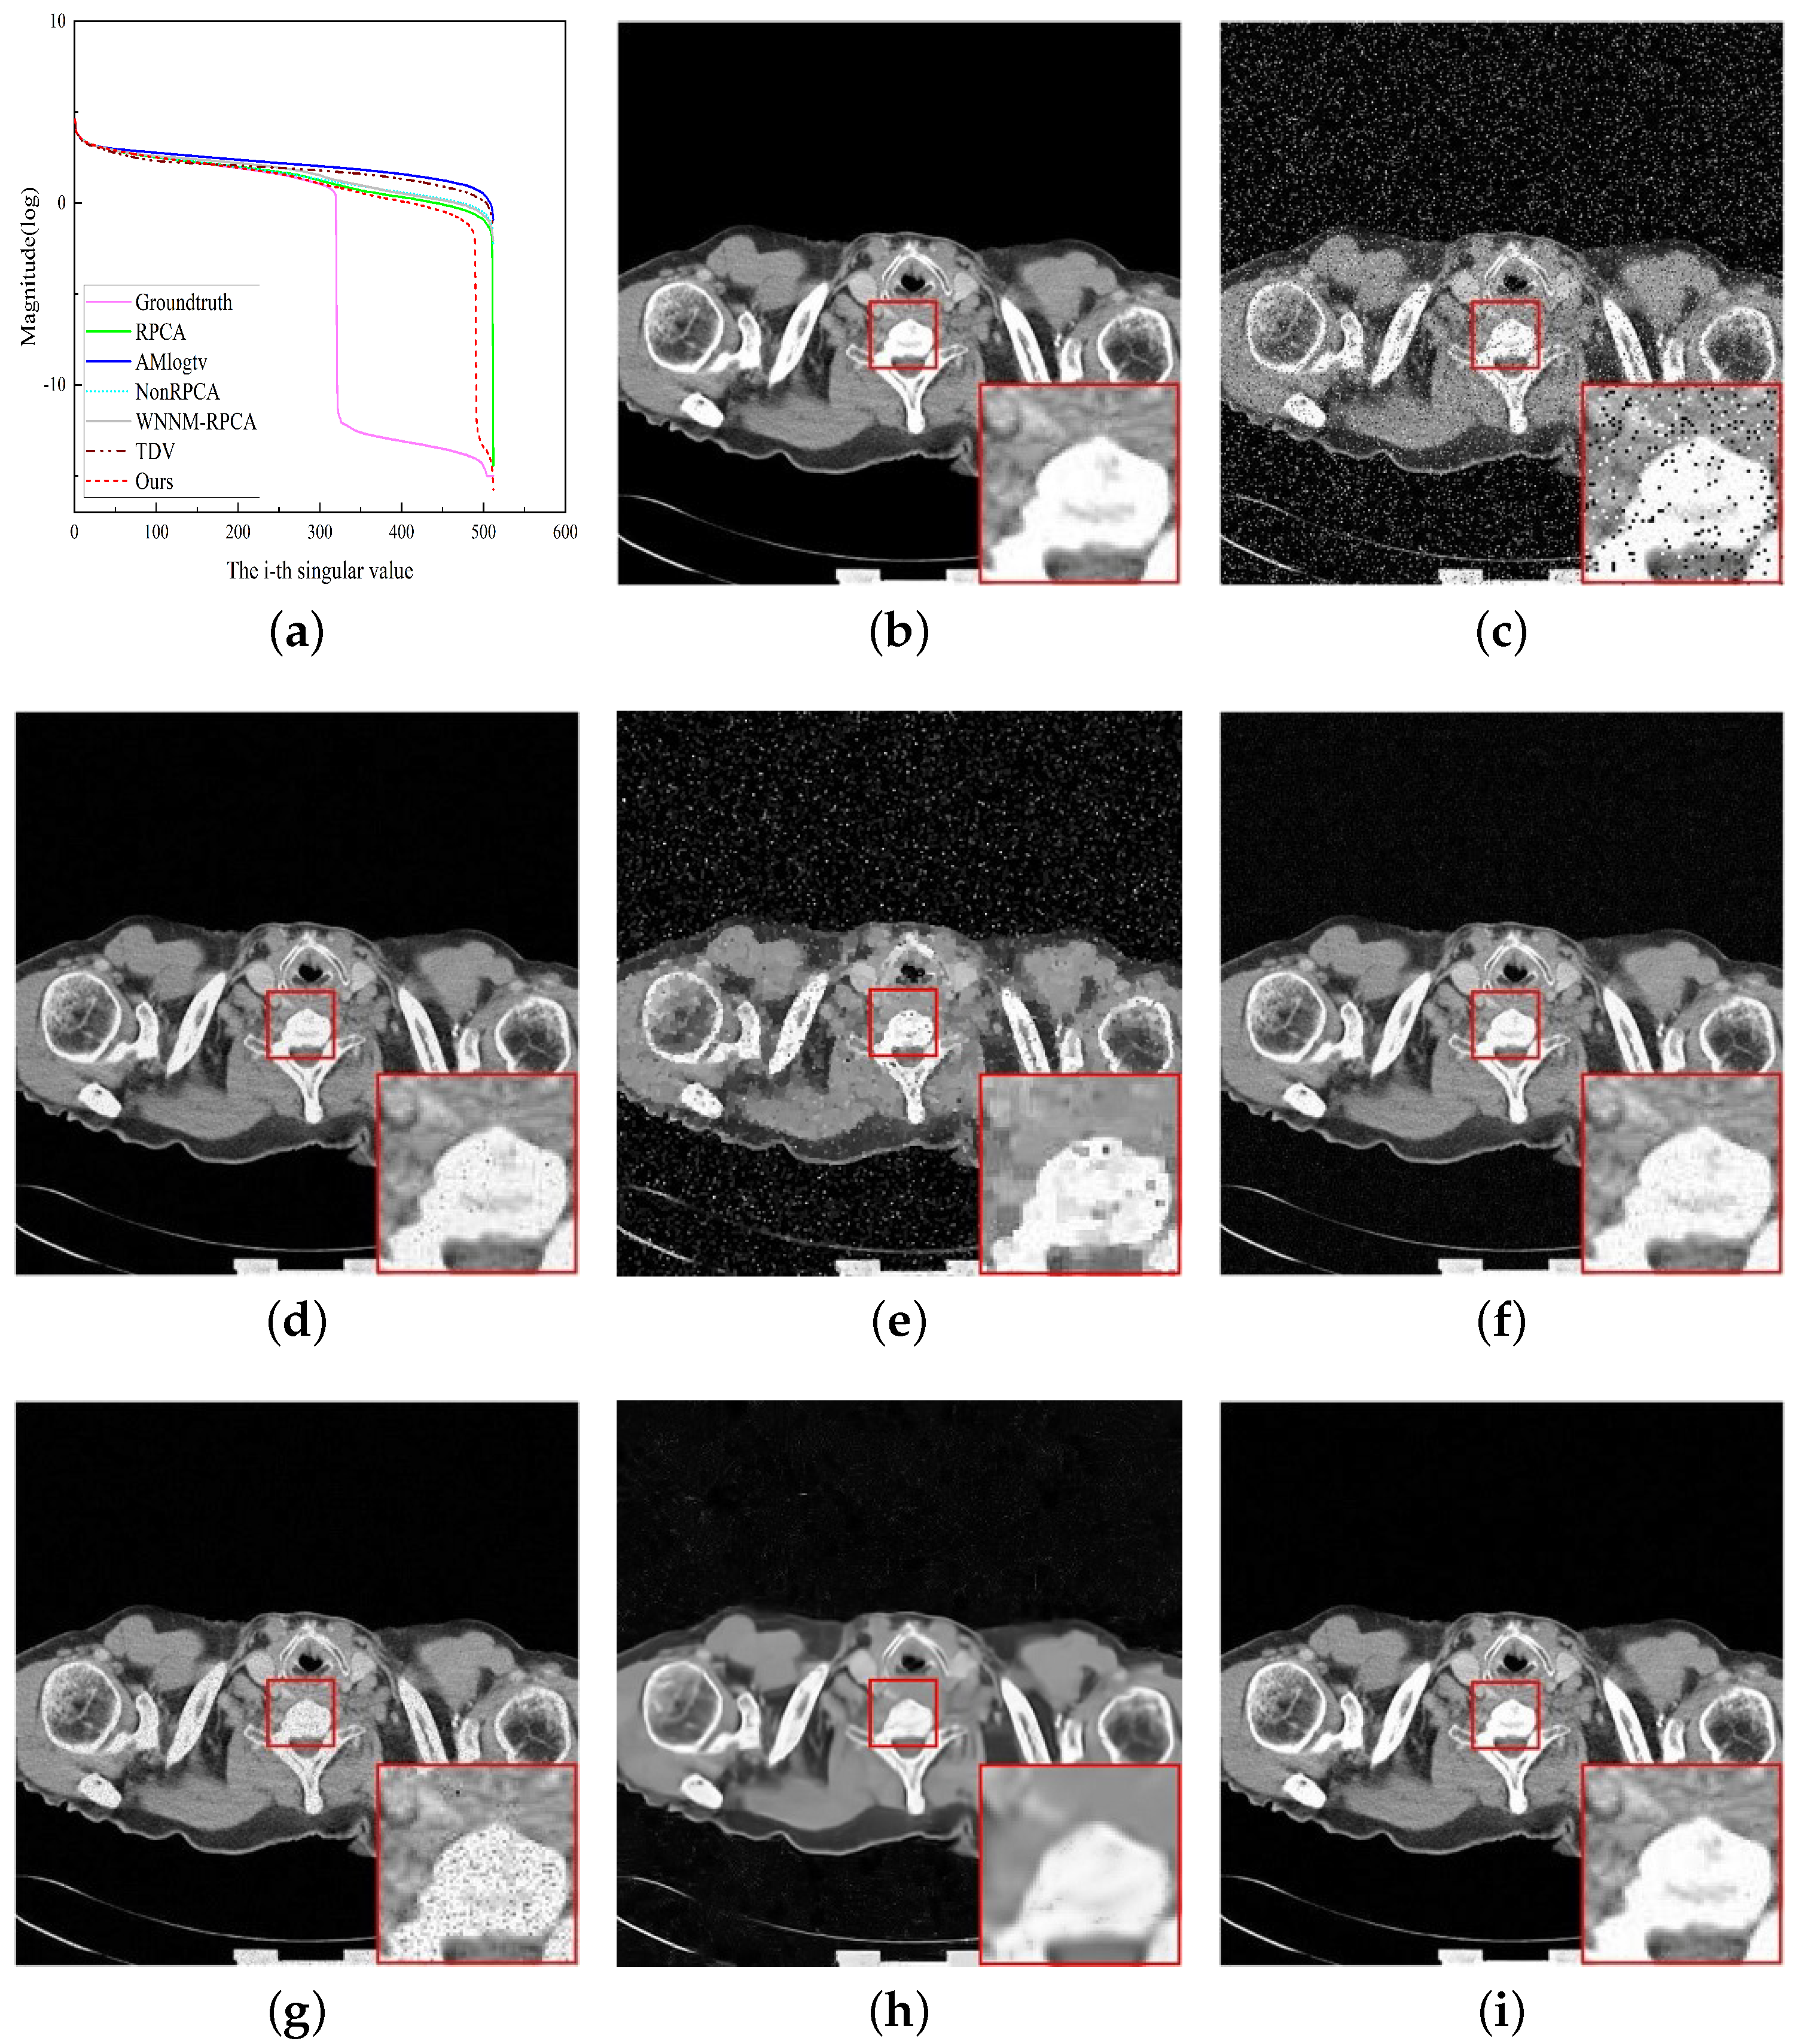

4.2. Medical Image Denoising